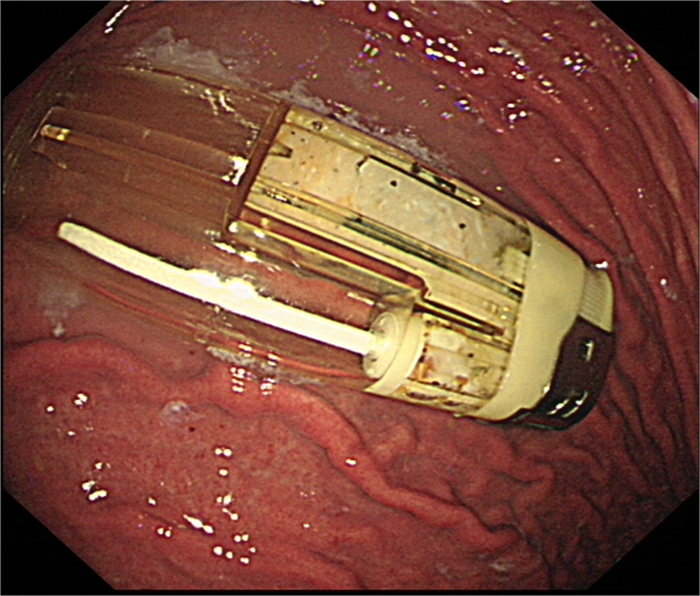

在全麻下电子胃镜进入胃内,可见1枚完整打火机,考虑到打火机较大,且边缘较硬,容易划伤贲门及食管黏膜,医生先使用异物钳夹住安全套,随胃镜进入胃内,将安全套套住打火机,异物钳夹住安全套开口处,随胃镜缓慢取出。后重新进镜观察,所经的贲门粘膜及食管粘膜无明显损伤,表明异物取出成功。